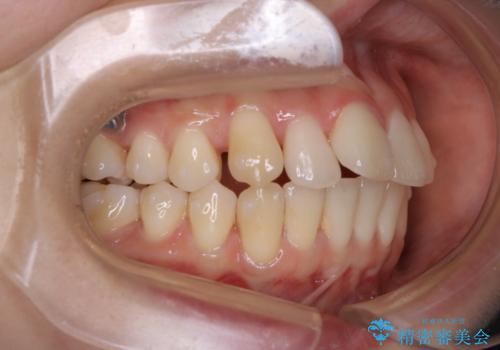

非抜歯でも劇的変化 インビザライン矯正治療

- 前歯のガタつきと噛み合わせの改善を主訴に初診来院され、審査の結果マウスピース装置による非抜歯での矯正を行うこととなりました。

元々の顎骨や口腔・歯槽骨が小さく、どうしても歯が並びきらない状況になっていました。マイクロインプラントという固定源からゴムかけを行うなど、補助装置を活用しながら臼歯部を順番に遠心方向(奥)に移動させていくことで抜歯をしなくても歯が並ぶよう計画を立てました。

歯のガタつきを治すため矯正治療を希望。審査の結果、非抜歯での矯正が可能であるという見通しが立ったためインビザラインによる非抜歯矯正治療を行った。

歯を並べるスペースを作るために、歯の遠心移動と歯列の拡大、歯自体を少しだけ小さく削る(IPR)という方法を複合的に組み合わせて配列を行いました。遠心移動用のゴムかけにはマイクロインプラントという小さいネジを用いて骨に直接固定源を求めました。